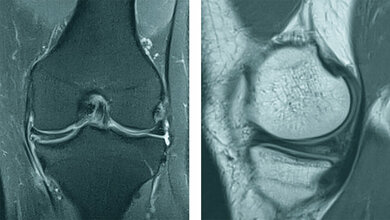

Schlüsselwörter: Persistierende Chorda dorsalis, Röntgen, CT, MRT

Keywords: Persist chorda dorsalis, x-ray, CT, MRI